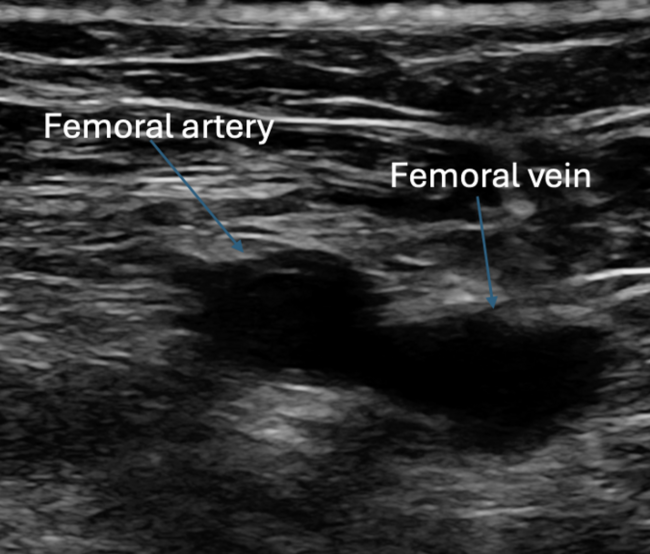

diagnosed 1.5 years prior. He was previously cardioverted and maintained on dronedarone with recurrence of symptomatic persistent AF, prompting referral for catheter ablation. He subsequently underwent AF ablation utilizing a pentaspline catheter. Ultrasound guidance was utilized to obtain 3 points of vascular access in the right femoral vein (Figure 1). ICE guidance was utilized for transseptal access and to guide catheter manipulation while ensuring optimal contact with ablation (Figures 2 and 3). Meticulous sheath management was employed, ensuring performance of all sheath exchanges while aspirating to reduce likelihood of air bubble introduction. A baseline electroanatomic voltage map was obtained for a substrate-based approach, which showed a predominantly healthy left atrium despite persistent AF though notably early in its course (Figure 4). There was spontaneous induction of AFL with a cycle length of ~280 ms and response to entrainment and activation mapping most consistent with typical AFL. The decision was made to proceed with PV isolation with confirmation of antral level isolation without significant encroachment on the posterior wall on a post-ablation voltage map (Figure 5). The cavotricuspid isthmus line was outlined on the EAM system with ICE while ensuring the intended ablation path was not in direct proximity to the right coronary artery. Ablation was then performed utilizing the pentaspline catheter in flower configuration after pre-administration of nitroglycerin and phenylephrine with termination of AFL and demonstration of bidirectional block post ablation. Total fluoroscopy time was ~4 minutes, the majority of which was utilized for the typical flutter ablation. The patient tolerated the procedure well and was discharged home 6 hours later. He continues to do well in outpatient follow-up.

Highlighted in this case are key tenets in our procedural approach to PFA. First, similar to other ablation technologies, the majority of complications are usually vascular in origin. These complications are largely mitigated with appropriate ultrasound guidance technique to vascular access, as was demonstrated in the MANIFEST-17k registry.16 The need for meticulous sheath management to reduce air bubble introduction cannot be overstated given the large sheath profiles utilized, to reduce the risk of stroke and coronary air embolism. We maintain that ICE guidance and EAM play a pivotal role in guiding ablation. This is important to ensure adequate contact for optimal energy delivery as there is increasing data highlighting its importance for durability.17